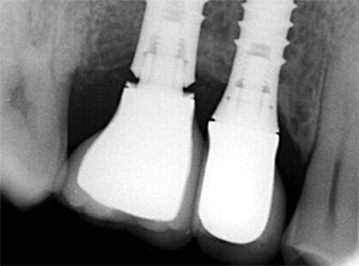

Este gráfico ilustra a mobilidade do implante-pilar a 120 N, indicando as mudanças de distância entre os pontos de referência após o carregamento de [µm] para três conexões individuais do pilar-implante. Indique o gráfico em barra que demonstra a conexão mais estável entre o implante e o pilar.